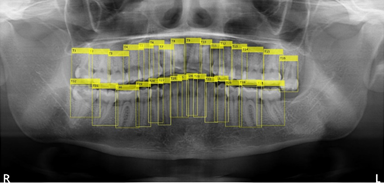

歯牙の自動認識結果

従来、歯科医院ではパノラマレントゲンの撮影後、歯科医師が目視で患者の歯牙情報をカルテや患者管理ソフトに入力し、診査・診断等を行っていました。本システムは、パノラマレントゲンの画像データから歯牙情報の有無をAI技術で自動解析し、また解析後の歯牙情報をアウトプットするものです。

本技術(特許出願中 出願番号:特願2020-132917)は、Springer Nature社のScientific Reportsに2020年11月6日付けで掲載された論文「Optimization Technique Combined with Deep Learning Method for Teeth Recognition in Dental Panoramic Radiographs」に基づきます。